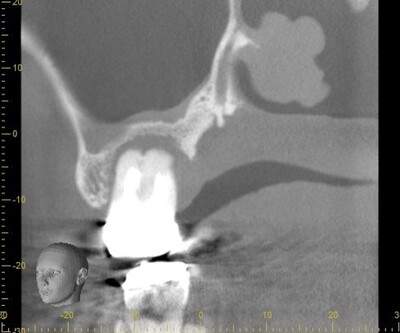

また、上顎の場合、膿が骨を溶かし、上顎洞まで交通することがあります。蓄膿症のような症状や顔がパンパンに腫れることもあります。

歯根破折④